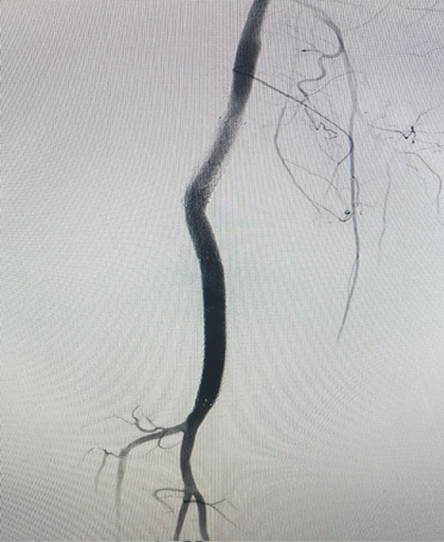

The patient was scheduled to undergo endovascular treatment of the popliteal artery aneurysm. Under general anesthesia, a right common femoral artery was antegrade punctured guided with a duplex ultrasound to perform the whole intervention percutaneously with a 6F 11cm sheat. After the puncture, the Perclose Proglideâ was inserted, in order to preload and guarantee the sealing of the puncture. Then, a 0,035”260cm Terumo â was used to perform the crossing over the distal arteries. The patient was heparinized with 5000UI intravenous in bolus. We performed a right limb arteriography to confirm the popliteal artery aneurysm (Figure 2). The popliteal artery was properly catheterized and we changed the guidewire for an Amplatz 0,035”260cm, in order to place a 11cm 11F sheat. After proper evaluation, two a covered self-expandable 8x100 and 10x75 Merit Wrapsodyâ were placed under roadmap into the distal popliteal artery and proximal femoral artery respectively, and post dilatated with a 8x100 and 10x100 catheter balloon Oceanus figures 3 and 4. There were no endoleaks, and the popliteal artery patency was identified. All the materials were removed, and we completed the final step of the perclose Proglideâ puncture closing. The patient was transferred to the nursery room, being discharged from the hospital two days after the surgery with no complications, femoral, popliteal and podal pulses present bilaterally, taking Rivaroxaban 20mg / day and Clopidogrel 75mg/day. After 1 month the patient was evaluated, presenting no further symptoms, no palpable mass in the right popliteal artery, and was submitted to a Duplex Ultrasound (Figure 5), that showed deep popliteal artery patency, stent patency, reduction of the aneurysm sac and no endoleaks. Furthermore, after one year follow-up, the patient remained asymptomatic, with Duplex Ultrasound showing popliteal artery with stent patency and no endoleaks. (Figure 6).

Figure 5: Duplex Ultrasound showing popliteal artery patency, stent patency and no endoleaks at 1 month.

Figure 6: Duplex Ultrasound showing popliteal artery patency, stent patency and no endoleaks at 1 year.